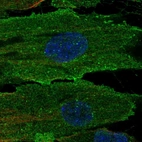

Immunohistochemistry analysis in human placenta and liver tissues using HPA051856 antibody. Corresponding CD248 RNA-seq data are presented for the same tissues.